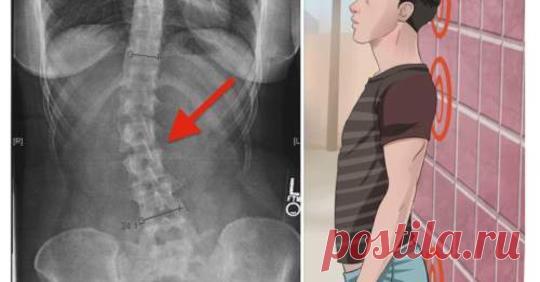

4 вещи, которые вы делаете неправильно, из-за чего возникает хроническая боль в спине, и как это исправить.

Хроническая боль в спине может серьезно ухудшить вашу жизнь. Это может повлиять на вашу физическую подвижность, ваше настроение, работу и отдых. Иногда боль может быть настолько сильной, что вы даже …